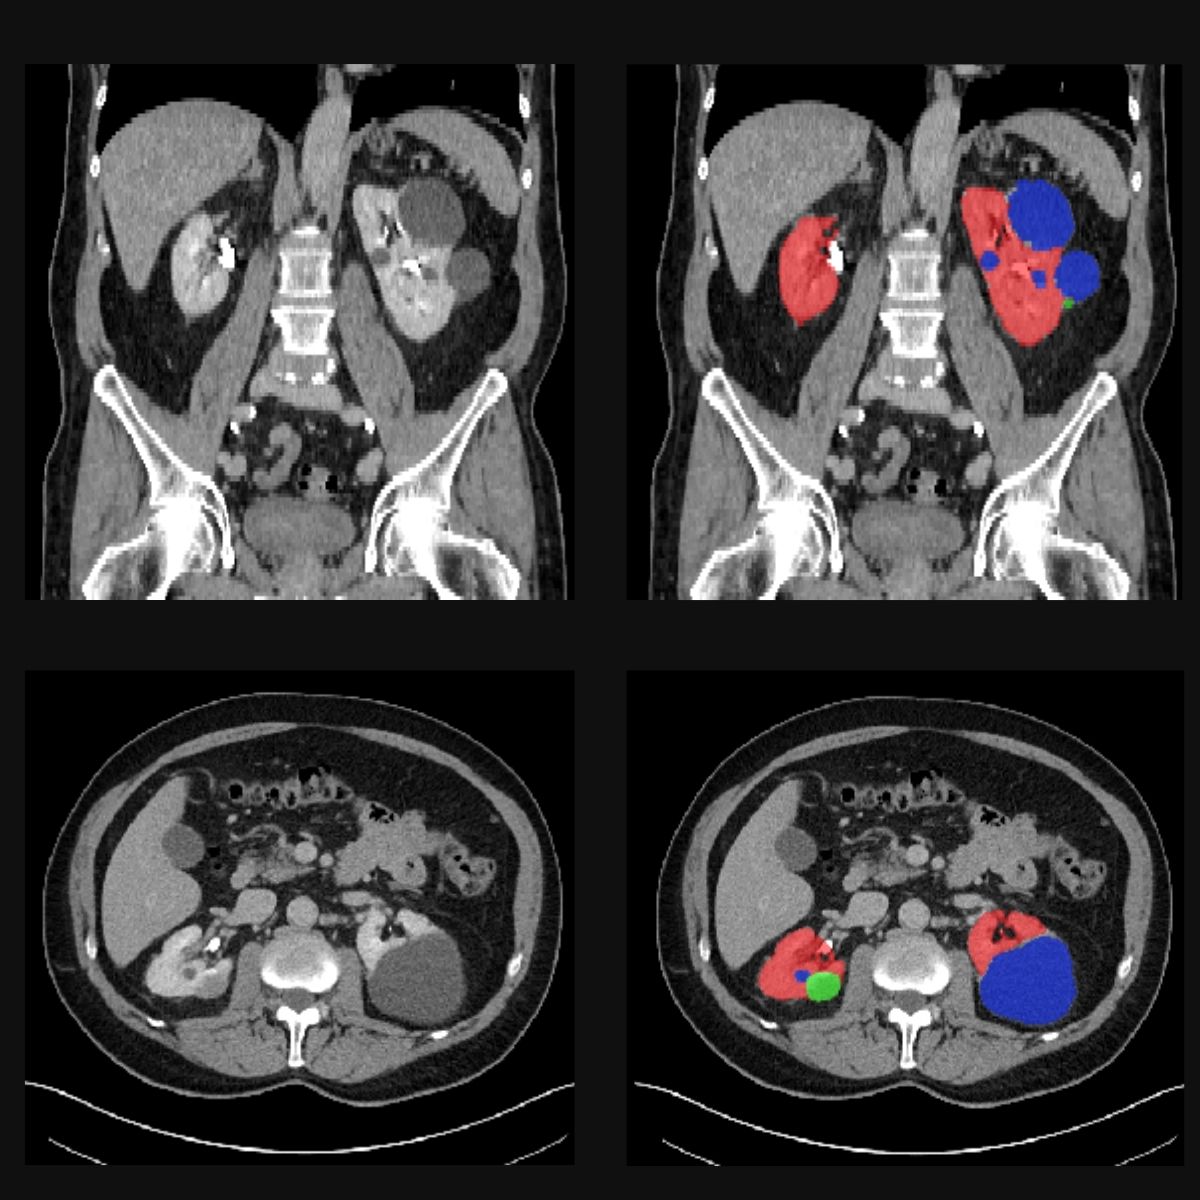

Our goal in COMFORT is to teach AI models to recognise tumours and other abnormalities to make diagnosis faster and more accurate. To this end, our experts manually annotate medical images from CT or MRI scans. This means they mannually outline the organs, in our case the kidneys and the prostates, and abnormalities such as cysts or tumours. By showing the AI model hundreds of annotated images, it eventually learns to generalise its knowledge to new images and recognise organs and tumours by itself.

In the images below you can see such scans: the red areas are the kidneys, green ones are turmours and blue ones are cysts.

Starting next year, we’ll test the model in a prospective study with data from real patients. The AI will work silently in the background, not influencing the diagnosis of patients. However, this will allow our team, to later compare the results of our model, with that of doctors, and assess how transparent AI might support clinical decisions in the future.